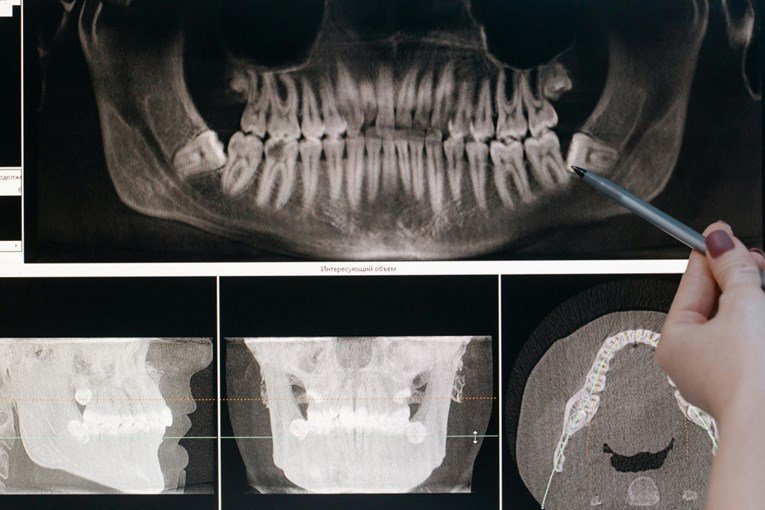

Tədqiqatın arxasında duran komanda ağız sağlamlığının əhəmiyyəti haqqında məlumatlılığı artırmaq istəyir. Mütəmadi olaraq diş həkiminə baş çəkmək, gündə iki dəfə dişlərinizi fırçalamaq və siqareti tərgitmək dişlərin sağlam olmasının açarıdır. Diş müayinələri yaşlı insanlarda xəstəlik və ölüm riskini izləmək üçün etibarlı üsul ola bilən dişlərin sayına və protezlər kimi həllərin tətbiqinə nəzarət etməyə imkan verir.